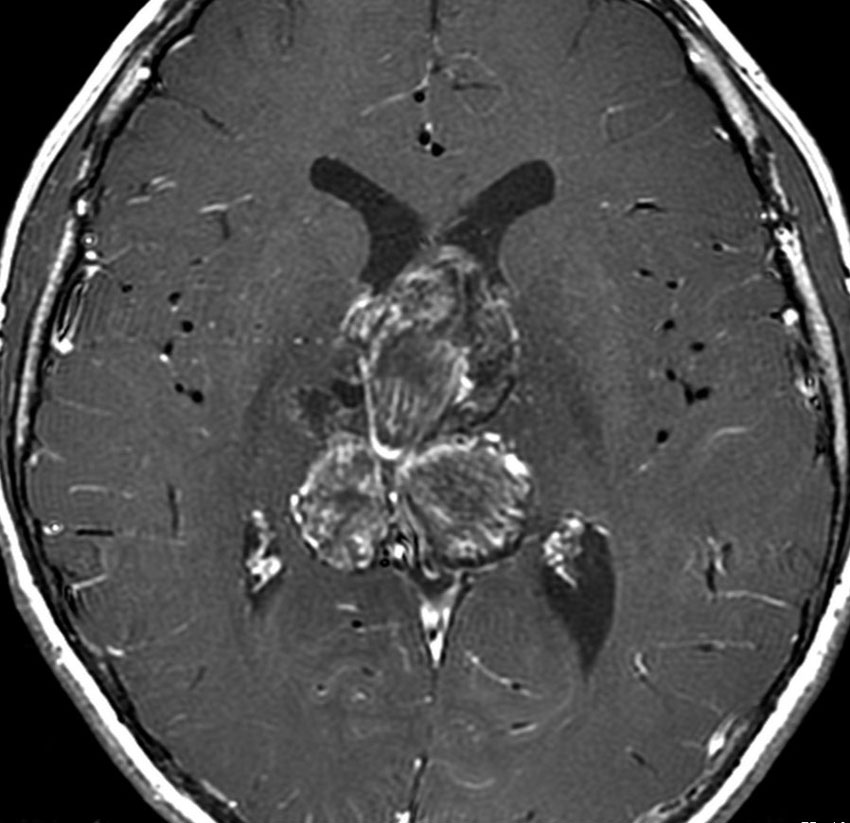

9歳男児の松果体奇形腫です。生検術と第3脳室開窓術を受けましたが,摘出術のリスクが高すぎるということで化学療法を6コース。2年間経過観察されましたが,腫瘍が増大しました。私のところへ来た時には,前後径73mmありました。

左からT2, swan, T1です。これが 類皮のう胞 dermoid cyst ということがわかります。類皮のう胞単独,あるいは成熟奇形腫の大部分としての類表皮のう胞は,かなり頻度の高いものです。松果体腫瘍で奇形腫を疑ったらまず,類皮のう胞の混在を疑います。それがあれば,かなりの確率で成熟奇形腫 mature teratomaです。

類皮のう胞は内部がほとんど皮脂,ケラチン,汗,毛髪なので,簡単に砕けるし,掻き出し吸い取ることができます。松果体成熟奇形腫の中では最も戦いやすい相手と言えるでしょう。再発しないようにするには,周囲ののう胞壁(真の腫瘍細胞)を完全摘出するしかありません。放射線も化学療法も何も効かないし,のこせば必ず再発します。

右迂回槽にちょっとdebrisは残っていますが完全摘出できました。病理は他の成分を少し混じる成熟奇形腫です。術後3年間再発はありませんし,学校へ通って体育もできています。

この手術はもちろん簡単ではありません,でもほとんどが類皮のう胞であるということがわかったので踏み込めたのです。